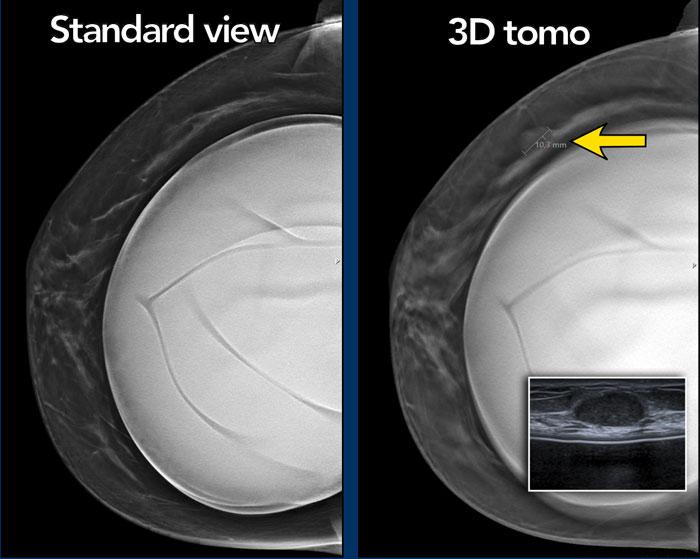

Chụp cắt lớp tổng hợp (Tomosynthesis)

Chụp cắt lớp tổng hợp có thể rất hữu ích như trong trường hợp này.

Có một khối ở phía bên ngoài, được thấy rõ nhất trên hình ảnh cắt lớp 3D.

Sinh thiết dưới hướng dẫn siêu âm đã được thực hiện và khối này được xác định là u xơ tuyến vú (fibroadenoma).